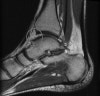

MRI : 발목 충돌증후군(Anterior impingement)

MRI에서 경도의 관절액 저류와 활막 증식이 확인될 수 있습니다.